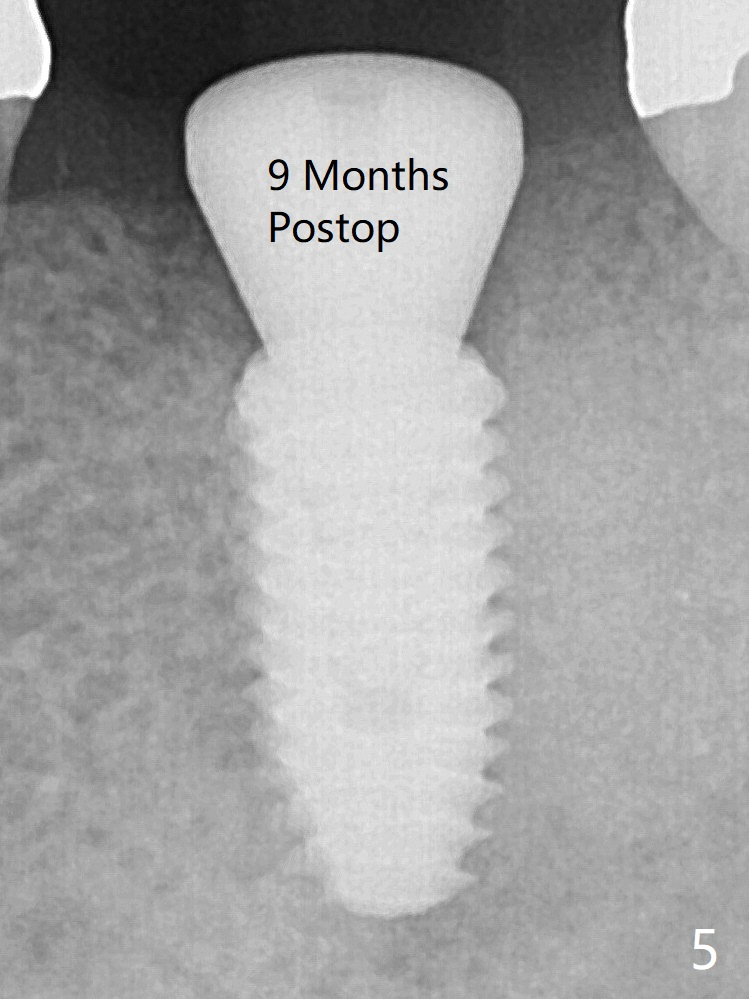

The bone is long enough to hold a 11.5 mm long implant. There is no difficulty in inserting the corresponding drill (4.5x11.5 mm) into the metal sleeve, but the lower right posterior teeth prevent the implant handpiece from going downward completely when the handpiece accesses lingually. Because of the extra manipulation, a 5x10 mm implant achieves insertion torque of ~ 20 Ncm (Fig.2). <: apical space. When the implant is placed initially according to the protocol/design, the implant is slightly supracrestal buccally. The implant is then seated apically ~.5 mm, which is unnecessary retrospectively. The bone density mesial to the implant (Fig2 *) increases 5 months postop (Fig.4), whereas that distal to the implant remains low 9 months postop (Fig.5). Bitewings taken 2.5 months post cementation (1 year postop, Fig.6,7) show subcrestal placement of the implant (advantage of guided surgery). The implant appears to be well protected; the crestal bone seems to cover the implant plateau (Fig.7 *). There will be little chance of thread exposure over years of use.